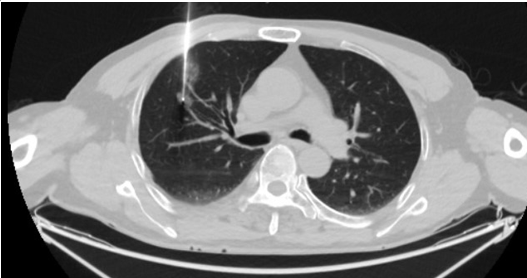

近日,我院呼吸与危重症医学科团队为几名老年患者成功实施了高难度CT引导下经皮同轴套管肺结节穿刺活检+射频消融术。该手术的成功实施,标志着我科在肺部肿瘤治疗领域又取得了新的技术突破,为无法耐受或不愿进行外科手术的肿瘤患者提供了新选择。

经多学科团队讨论,为患者制定微创治疗方案。张倩主任团队为患者实施CT引导下经皮同轴套管肺结节穿刺活检+射频消融术,一次穿刺即能明确病灶性质,又能进行肿瘤微创治疗,避免了多次穿刺引起的不适及并发症的发生,患者恢复快,住院时间短,大大降低患者的医疗费用。

肺癌的射频消融治疗术指的是在CT机引导和监视下,将射频消融针经皮肤穿进肺的肿瘤组织内,在短时间内杀伤肿瘤细胞彻底使其失去活性。从而达到不开刀根治肿瘤的目的。同步经皮肺同轴活检穿刺技术是经胸壁穿刺入肺,以最小的创伤准确获得肺占位病理学诊断使用的技术。